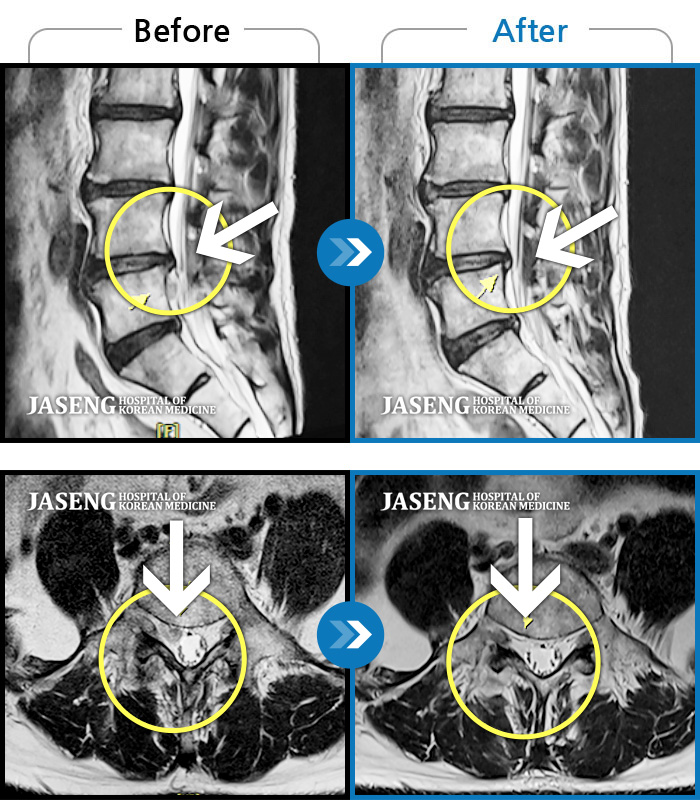

Before

After

양측 허리 통증과 좌측 허벅지부터 발바닥까지 송곳으로 찌르는 듯한 통증 지속되어 내원하셨습니다.

2023.12.26 ~ 2024.12.05